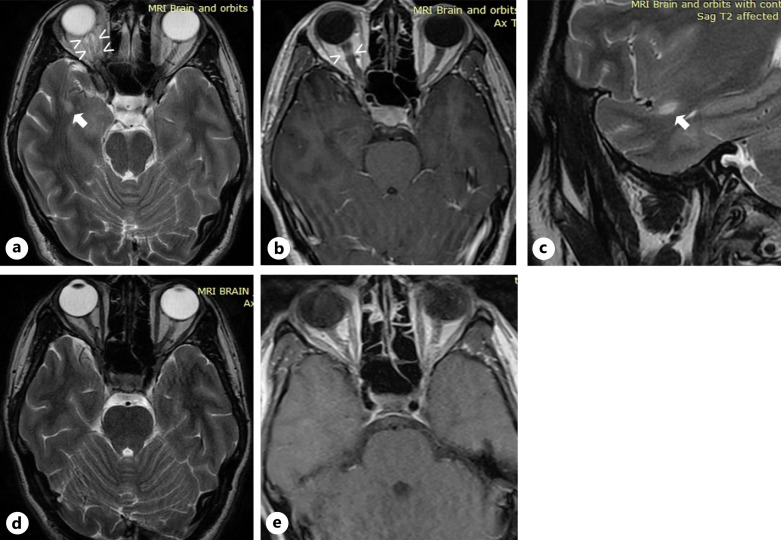

Case presentation: In this study, we describe the case of a 27-year-old woman who presented with signs and symptoms of optic neuritis and was then diagnosed with both MS and NF1. As the patient continued to experience MS relapses despite initial interferon-beta treatment, she was subsequently switched to natalizumab and responded well.

Conclusion: This case illustrates how MRI lesion differentiation with the co-existence of MS and NF1 can be difficult due to overlaps in lesion characteristics, while treatment decisions can be challenging mainly due to scarce data on the oncogenic risk of MS immunomodulary therapies. Therefore, clinicians need to balance out the risk of malignancy development with the risk of progressive neurological disability when treating such patients.